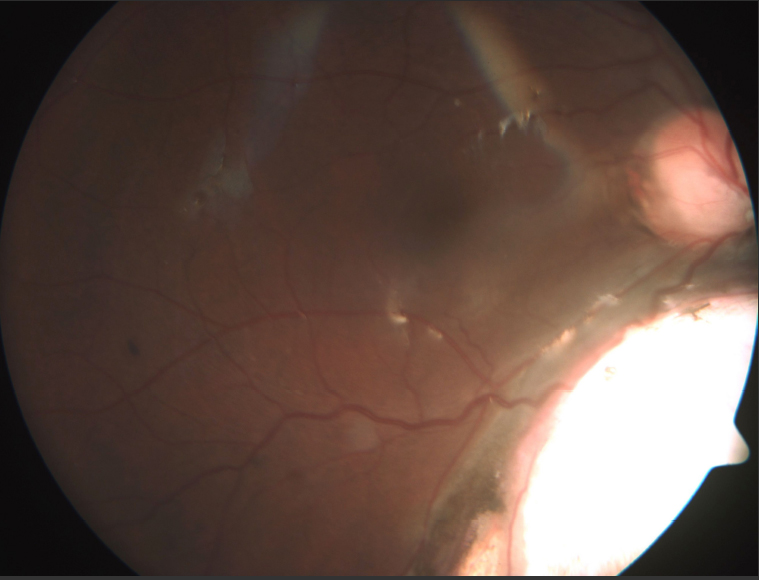

Figure 2 of Kumar, Mol Vis 2011; 17:1414-1419.

Figure 2. Fundus photograph in type III coloboma.